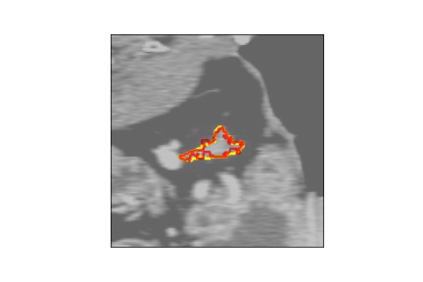

The human annotations are imperfect, especially when produced by junior practitioners. Multi-expert consensus is usually regarded as golden standard, while this annotation protocol is too expensive to implement in many real-world projects. In this study, we propose a method to refine human annotation, named Neural Annotation Refinement (NeAR). It is based on a learnable implicit function, which decodes a latent vector into represented shape. By integrating the appearance as an input of implicit functions, the appearance-aware NeAR fixes the annotation artefacts. Our method is demonstrated on the application of adrenal gland analysis. We first show that the NeAR can repair distorted golden standards on a public adrenal gland segmentation dataset. Besides, we develop a new Adrenal gLand ANalysis (ALAN) dataset with the proposed NeAR, where each case consists of a 3D shape of adrenal gland and its diagnosis label (normal vs. abnormal) assigned by experts. We show that models trained on the shapes repaired by the NeAR can diagnose adrenal glands better than the original ones. The ALAN dataset will be open-source, with 1,594 shapes for adrenal gland diagnosis, which serves as a new benchmark for medical shape analysis. Code and dataset are available at https://github.com/M3DV/NeAR.